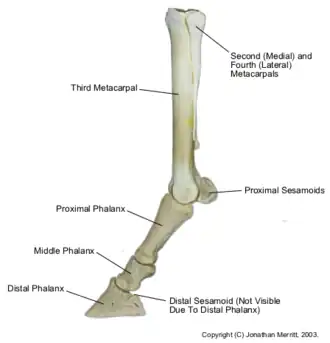

In the horse it occurs at the horse's fetlock. The sesamoid bones lie behind the bones of the fetlock, at the back of the joint, and help to keep the tendons and ligaments that run between them correctly functioning.

Usually periostitis (new bone growth) occurs along with sesamoiditis, and the suspensory ligament may also be affected. Sesamoiditis results in inflammation, pain, and eventually bone growth.

In horses, sesamoiditis is generally caused by excess stress on the fetlock joint. Conformation that promotes sesamoiditis include long pasterns, or horses with long toes and low heels.